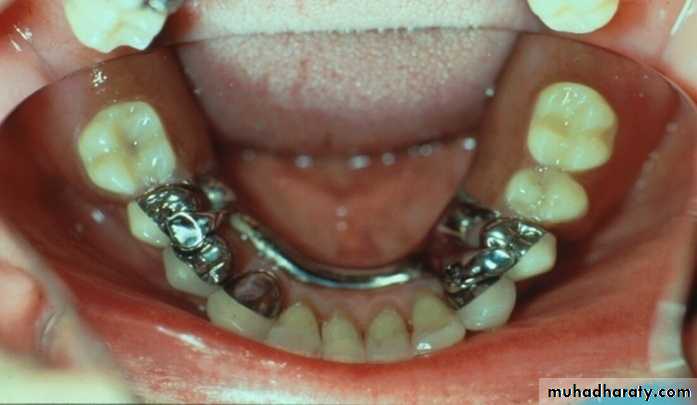

Bar Attachments

►Bar attachments consist of :A bar

Retentive clip(s)Definition of bar attachments

Advantages of Bar Attachments

* Excellent retention & stability for the prosthesis.* The bar acts as an indirect retainer & provides vertical support for the prosthesis preservation of the alveolar bone.

* Rigid splinting & constant mechanism of abutment stabilization

Bar Joints

Bar Units* Resilient version

* Some rotational movement

between the bar & the sleeve

more R.R support

Less torque on teeth

* Rigid version

* provides rigid fixation – no

movement between the bar &

the sleeve indicated

when saddle gap is long